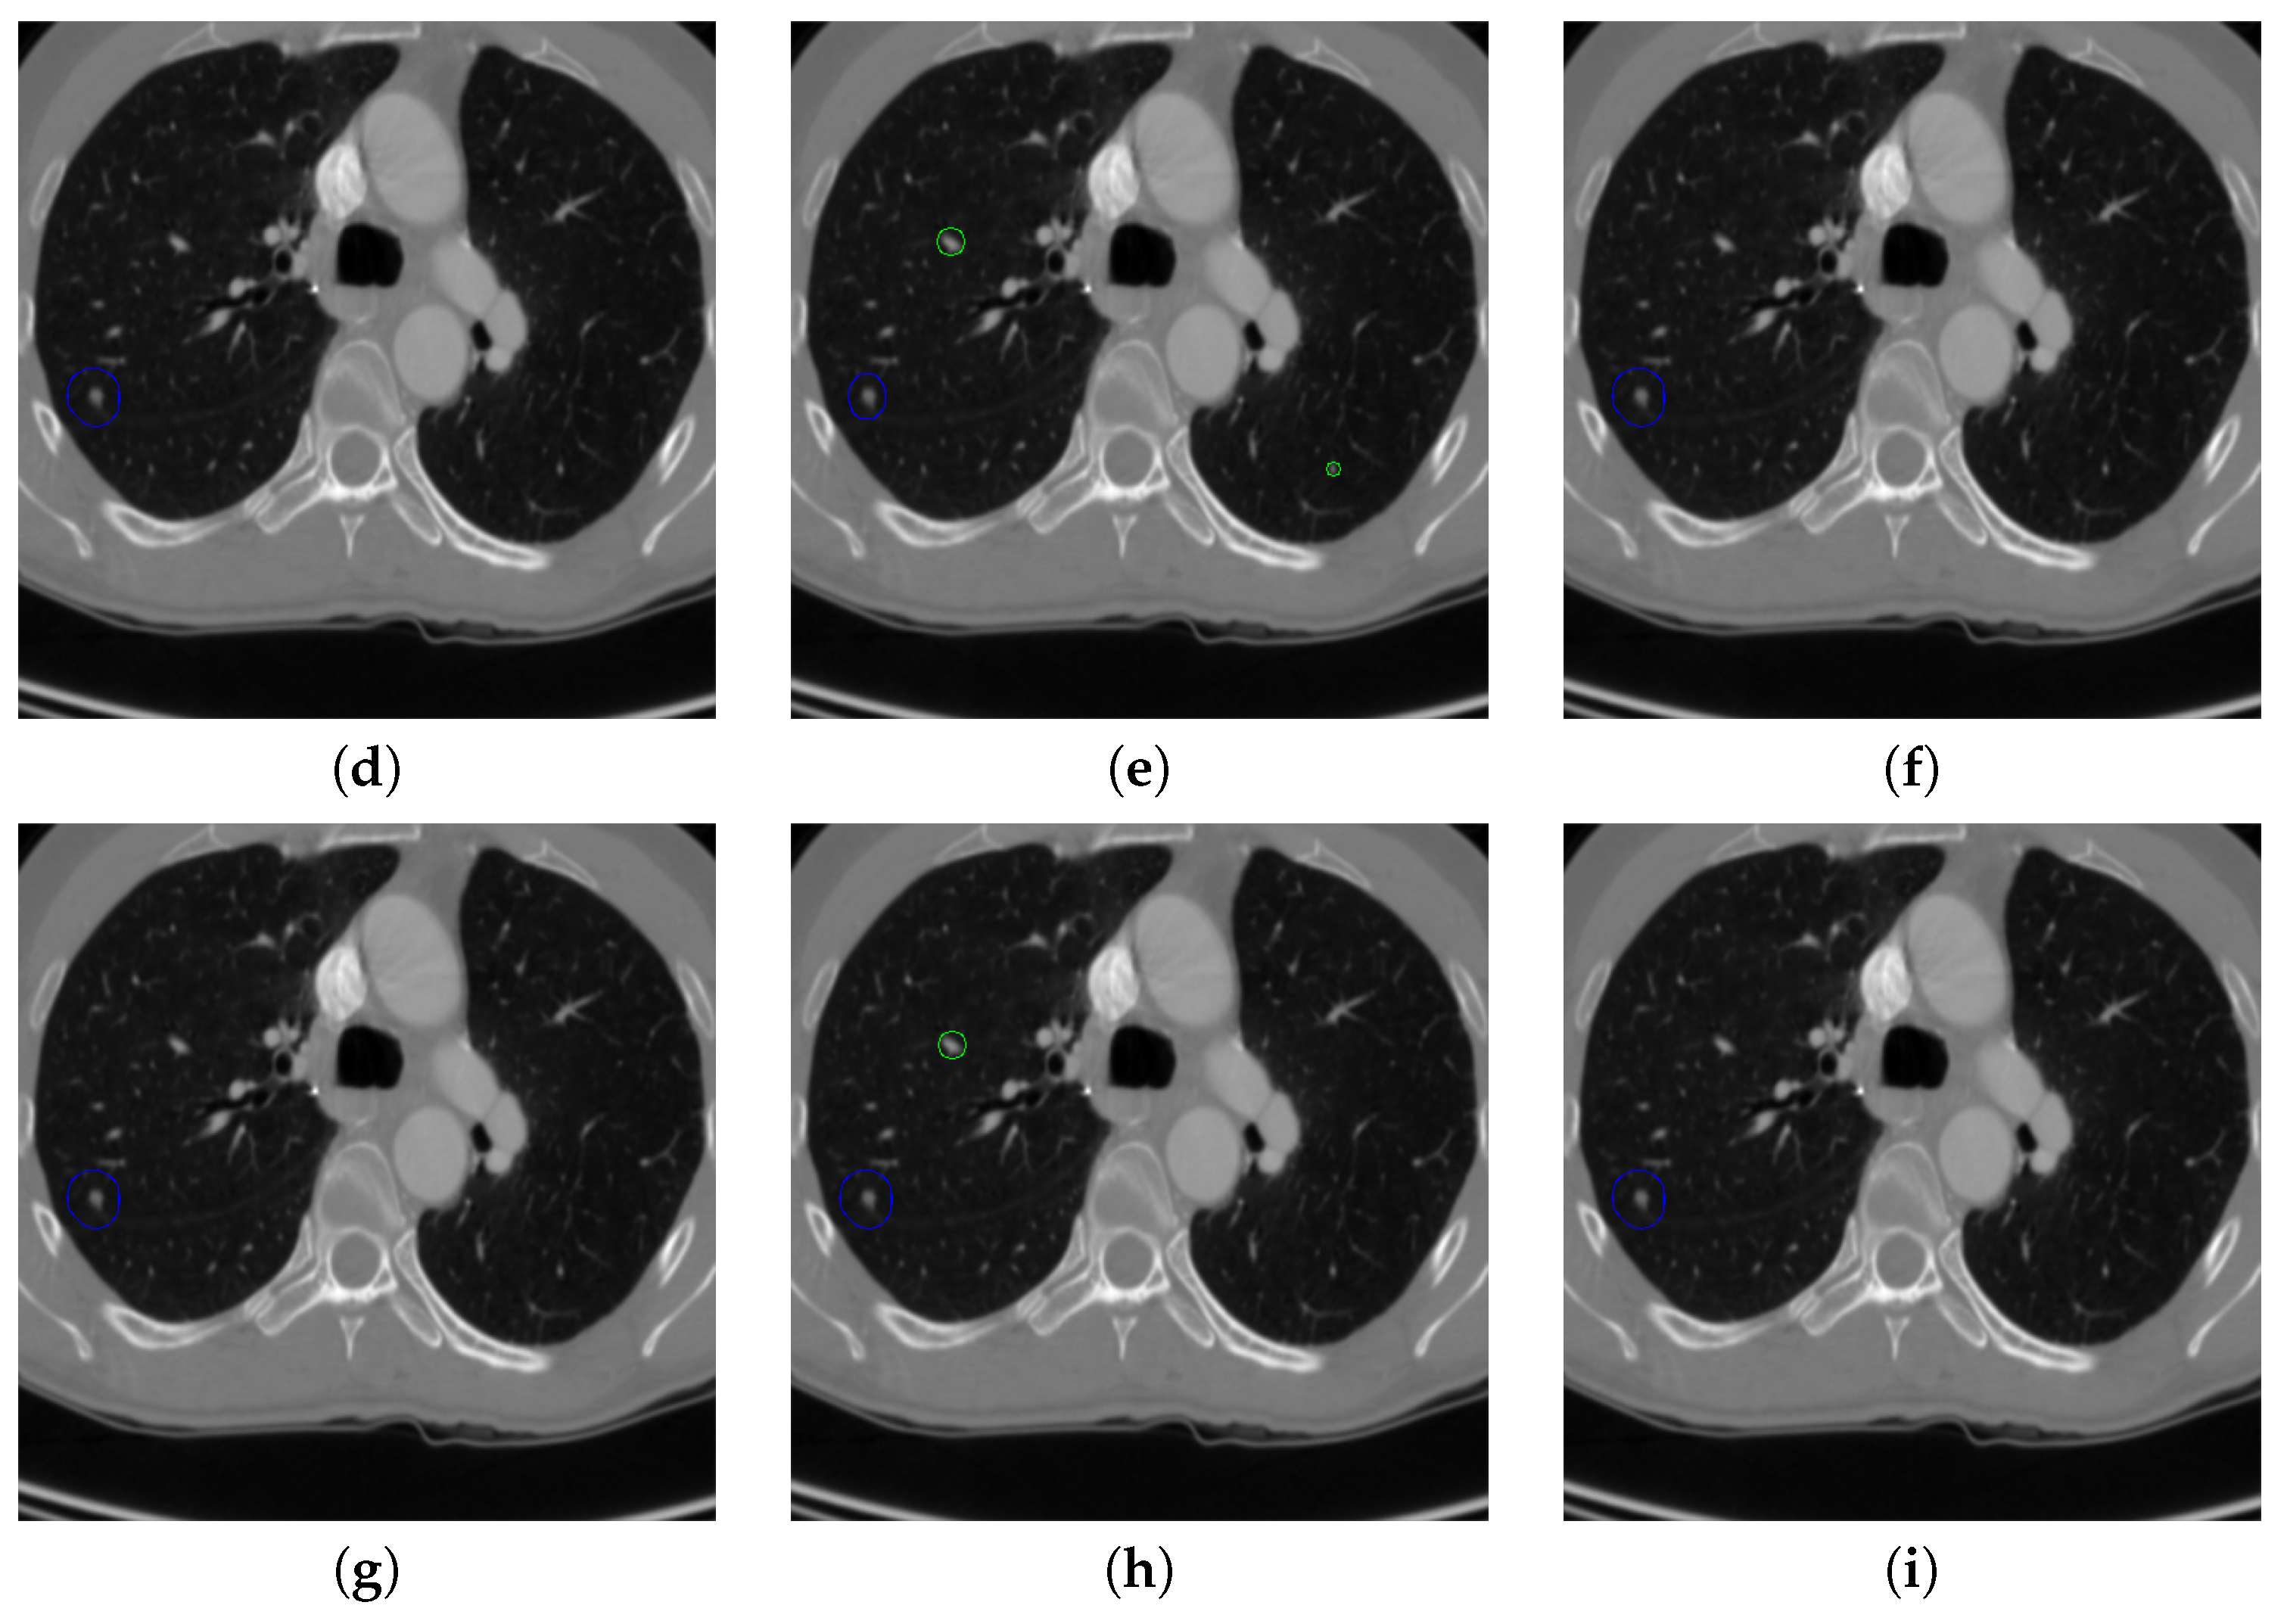

Figure 17 and Figure 18 illustrates the performance of pulmonary nodule detection by different methods on two example images in the LUNA16 dataset. In addition, Figure 19 and Figure 20 illustrates the performance of pulmonary nodule detection by different methods on two examples images in the TianChi dataset. As marked by green circles in Figure 18b,c and Figure 19c, the 3D-FCN and MR-CNN directly detected the nodule candidates from the original CT image without pre-processing, resulting in the incorrect determination of non-nodule tissue outside lung as nodule since the outside-lung organs are not filtered out from the nodule candidates. The 3D-UNET and PRN-HSN add the lung parenchyma region segmentation stage before detecting the nodule candidates inside-lung, so they provide better performance than 3D-FCN and MR-CNN in decreasing the over-estimation rate. However, they still suffer from unsatisfactory results for the following reasons: (1) the lung parenchyma segmentation is generated by simple thresholding with morphological operations so the near-edge regions are lost, shown as the one marked by yellow circle in Figure 20d,e; (2) the convolution kernel used in nodule candidate detection of 3D-UNET is with a small receptive field to learn global features from the image, so it is likely to confuse some small tissues as true nodules with small sizes, shown as the one marked by green circle in Figure 18d and Figure 20d; and (3) the proposed hierarchical saliency network (HSN) in PRN-HSN for nodule candidate classification omits the information with different resolutions, resulting in that the small-size nodule within the weakened, low-resolution region cannot be correctly recognized, as shown by the yellow circle in Figure 18e. The DCNN method simply applies the Faster RCNN method to provide good performance with low computational cost, but it may omit the nodules on the parenchymal edge shown as yellow circles in Figure 20f. CLAHE-SVM method adds a contrast-enhancement pre-processing before the nodule detection, leads to better performance on detecting nodules in the low-contrast region. However, it is easily to over-enhance the small-size tissues and over-estimate them as nodules, as shown by the green circles in Figure 19g andFigure 20g. The detection is also implemented over the whole image, so the nodule on the parenchyma edge may be under-estimated show by the yellow circle in Figure 20g. The Mask-RCNN method provides better effects than the above methods because of the good performance of Mask-RCNN in object detection. However, the performance is not stable for the small-size tissues and the irregular-shape nodule, shown by the green circles in Figure 17h and Figure 19h, and the yellow circle in Figure 19h. The proposed method takes the advantage of a series of U-Net-like networks to perform the nodule detection following a “coarse-to-fine” order of inside-lung region detection, nodule candidate detection and nodule determination. The U-Net network is modified by embedding inception structure, replacing the convolution and pooling by dilated convolution, and adapting multi-scale pooling and multi-resolution convolution connection, for different requirements of the three stages, respectively. Moreover, it makes use of the MSE loss, VGG-19-based perceptual loss as the complement of dice loss to optimize the whole framework. Therefore, as shown in Figure 17i, Figure 18i, Figure 19i and Figure 20i, the proposed framework provides superior performance on pulmonary nodule detection with low over-estimation of non-nodule tissues at the same time.

Figure 19. The result of detecting pulmonary nodules by different methods on one example image in TianChi dataset. Red circle represents the ground truth region of nodules, blue circles represent the correct estimation of pulmonary nodules, green circles represent the over-detected nodules, while yellow circles denote the nodules being omitted. (ai) are: ground truth nodule in the given chest CT image, nodule detected by 3D-FCN, MR-CNN, 3D-UNET, PRN-HSN, DCNN, CLAHE-SVM, MASK-RCNN and our proposed method.